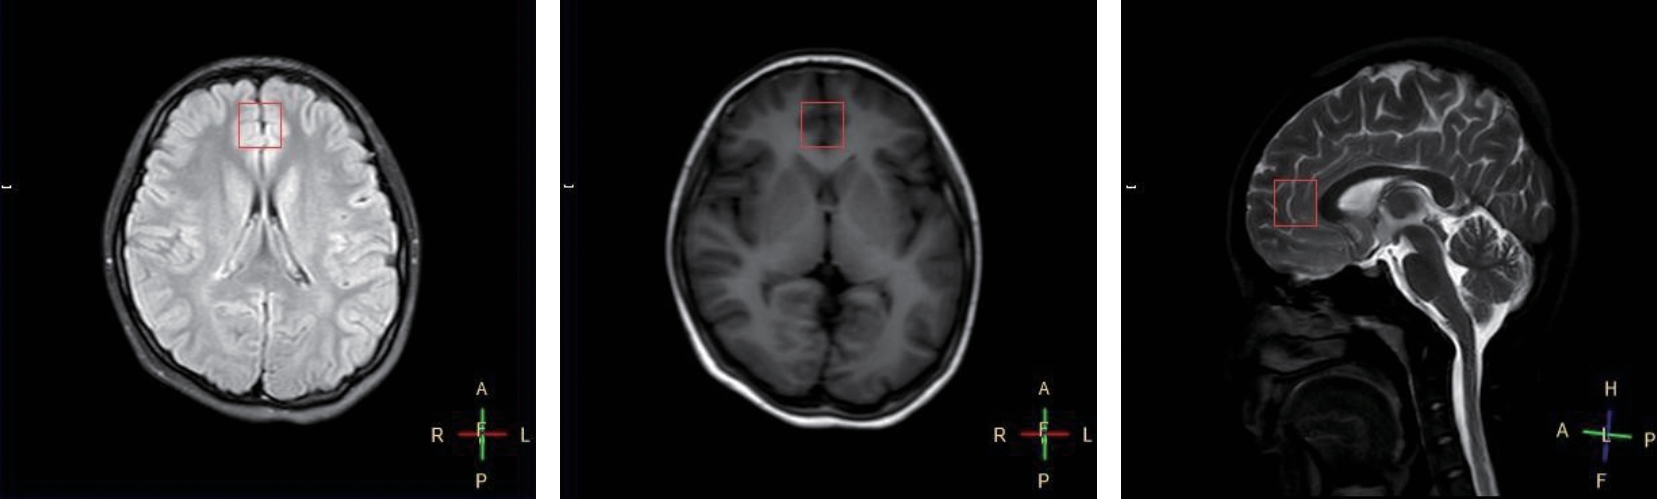

• 青少年双相障碍抑郁发作患者神经代谢的性别差异研究

摘要 (260) HTML (19) PDF 1.38 M (124) 评论 (0) 收藏

摘要:目的 探讨青少年双相障碍抑郁发作患者性别差异与腹内侧前额叶(vmPFC)神经代谢之间的关系。方法 招募2023年6月—2024年6月符合精神障碍诊断与统计手册第5版双相障碍抑郁发作诊断标准,且近1个月未接受任何治疗的45例青少年双相障碍抑郁发作患者作为研究对象,其中男性患者20例,女性患者25例。采用汉密顿抑郁量表-24对入组患者的抑郁症状严重程度进行评估,应用氢质子磁共振波谱(1H-MRS)扫描检测vmPFC内肌醇(mI)、胆碱(Cho)、N-乙酰天门冬氨酸(NAA)、肌酸(Cr)水平。结果 女性患者与男性患者的年龄、独生率、居住地、受教育程度、发病年龄、病程、家族史及HAMD评分比较,差异均无统计学意义(P >0.05);女性患者与男性患者NAA/Cr水平的比较,差异有统计学意义(P <0.05);男性患者vmPFC的mI/Cr与病程呈负相关(rs =-0.467,P <0.05),男性和女性患者Cho/Cr与HAMD评分均呈正相关(r =0.553和0.621,均P <0.05)。结论 女性青少年双相障碍抑郁发作患者vmPFC脑区可能存在更高的神经代谢物NAA的水平。